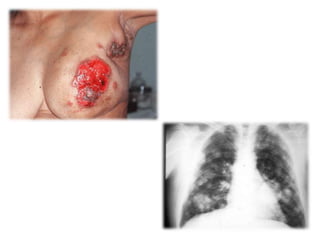

Este documento describe las diferentes fases del cáncer de mama, desde la fase inicial hasta la más avanzada. La fase I se refiere a tumores menores de 2 cm sin extensión a los ganglios linfáticos. La fase II implica tumores menores o mayores de 2 cm que se han extendido a los ganglios linfáticos locales. La fase III representa tumores que se han extendido más allá de los ganglios linfáticos locales a otras partes del cuerpo.